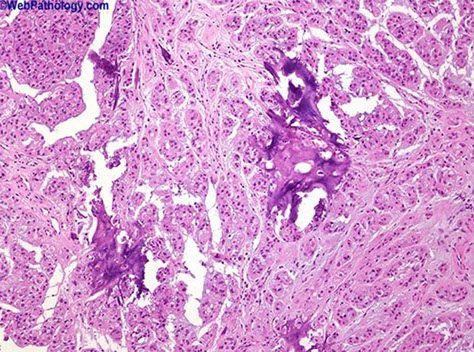

Gross: more variegated and smaller than seminoma c hemorrhagic / necrotic foci

- frequently extends through tunica albuginea into epidydmis / cord

Micro: looks like it is falling apart from low power, very ugly tumor with lots of cell overlap

- alveolar / tubular patterns c papillary convolutions

- sheets of cells if undifferentiated

- no well-formed glands; no nesting (as in seminoma)

- indistinct cell borders

- lots of variation in cell size / shape and atypical mits c frequent overlapping nuclei

IHC: (+) OCT3/4, PLAP, SALL4, CK, CD30 (can diminish c chemotx), CAM5.2, AE1/AE3, SOX2

- negative: KIT, CD117, SOX17, EMA, D2-40 (var)